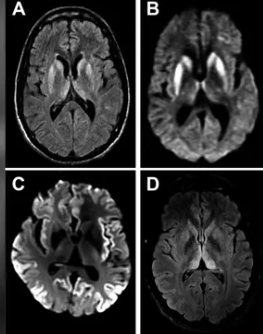

그녀는 MRI(자기공명영상) 검사 결과 뇌 손상이 발견됐고 추가 검사에서 ‘프리온’ 단백질 양성으로 밝혀졌다. 프리온은 세포를 둘러싼 세포막에 있으며 세포 통신 및 상호 작용에 관여하는 분자다.